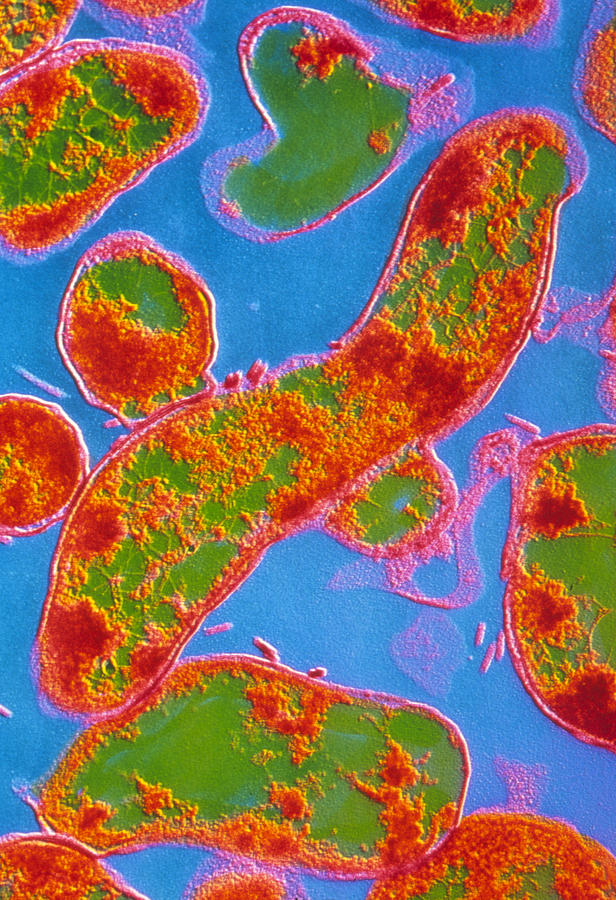

Кампилобактер фетус: патогенез и инфекции